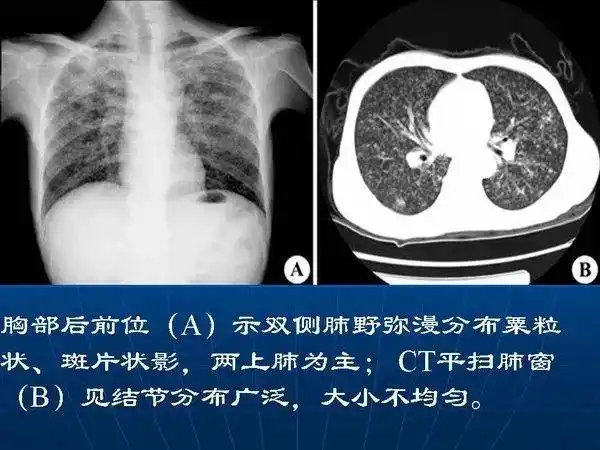

胸片诊断肺结核还是肺炎 - 聚图网